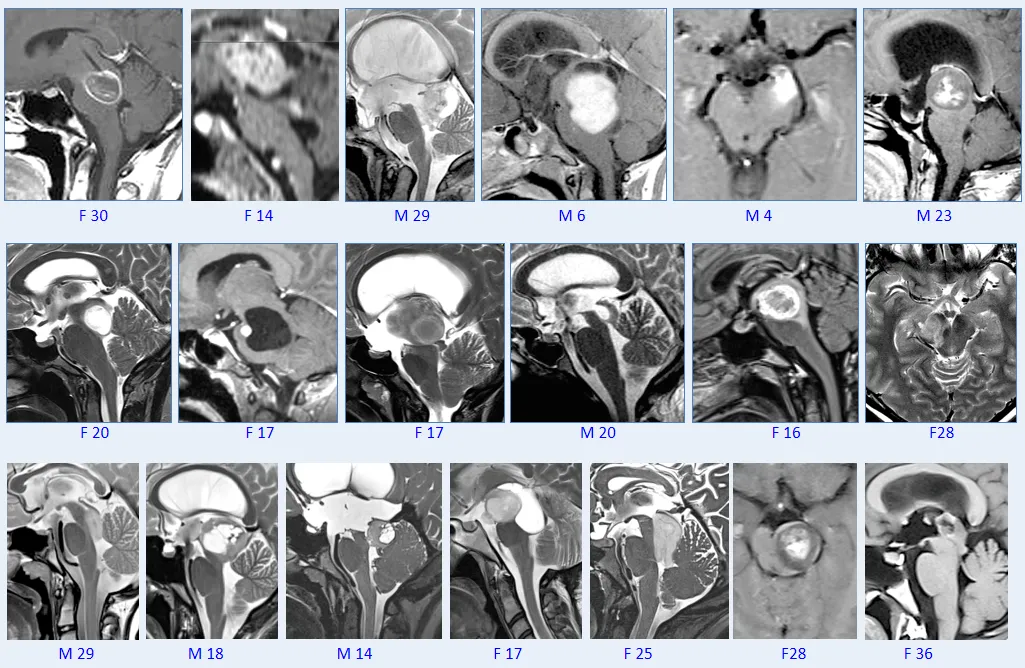

▼巴教授脑干毛星50+例影像图汇

1.脑干不是“无人区”!

2.显微手术在局灶性脑干胶质瘤的整体管理中发挥着重要作用。

3.”低级别“胶质瘤是合适的手术候选者。

4.在许多情况下,可以尝试并实现治愈。